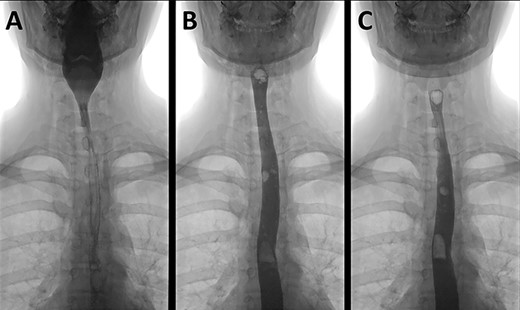

A water-soluble contrast swallow examination demonstrating contrast passing from the pharynx (A) through the oesophagus (B and C) with no evidence of leak.

Nasendoscopy to the level of the vocal cords did not reveal an obvious source of air leak. Neither an enhanced CT thorax and abdomen following oral gastrograffin contrast, nor a water-soluble contrast swallow examination (Fig. 3) showed any evidence of contrast leak or identify a source of perforation.